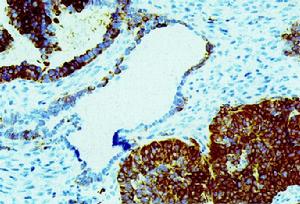

Sertoli-Leydig細胞瘤6 Sertoli-Leydig細胞腫瘤伴網狀成分。性索區域抑制素呈強陽性,而網狀區域為弱陽性